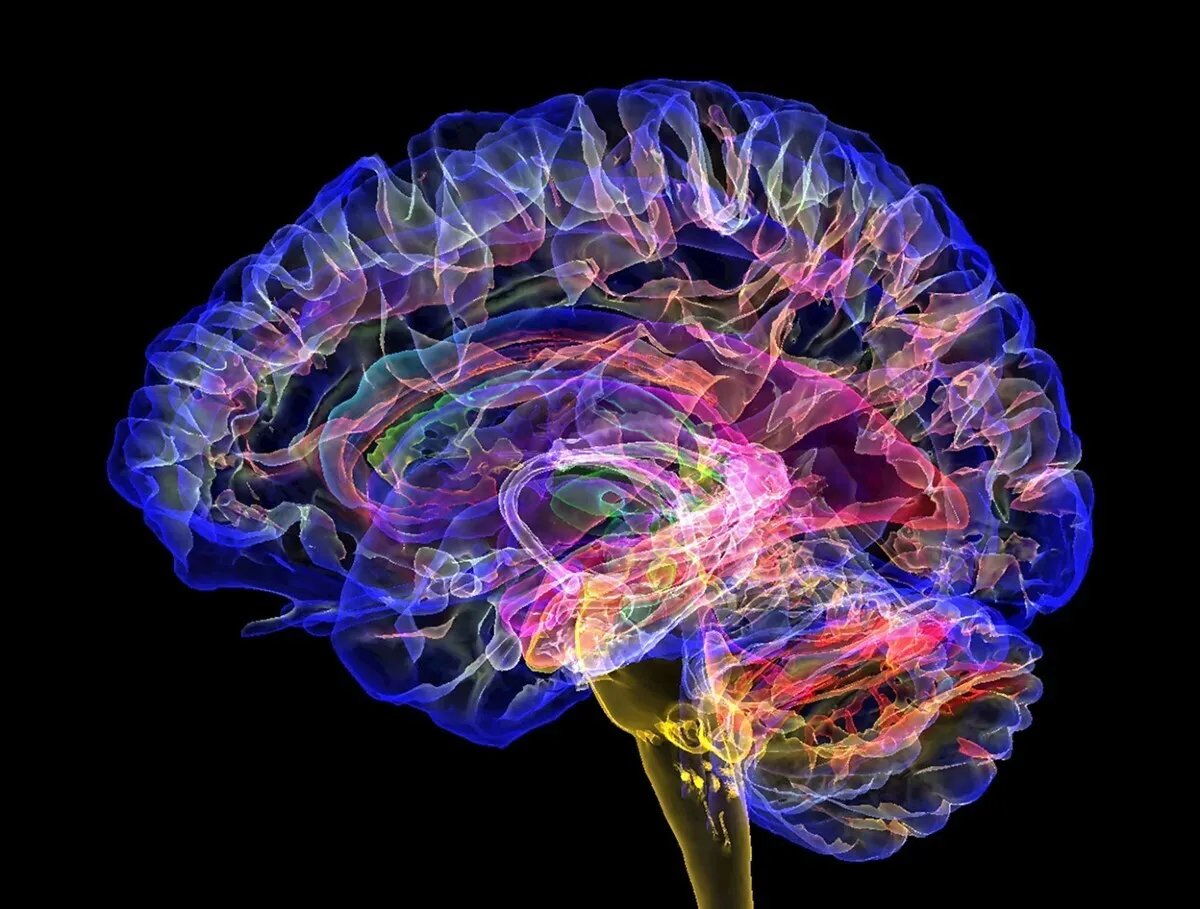

Using direct intracranial brain recordings in humans, a new study has identified the thalamus, a small, deeply situated brain structure, as a key player in conscious perception. The researchers found that specific higher-order regions of the thalamus function as a gateway to awareness by transmitting signals to the prefrontal cortex, the journal Science reported.

These findings offer important insights into the complex nature of human consciousness. Unraveling the neural basis of consciousness remains one of neuroscience’s greatest challenges. Prior research has proposed that consciousness consists of two main components: the conscious state (such as being awake or asleep) and conscious content (the specific experiences or perceptions one is aware of).

While subcortical structures are primarily involved in regulating conscious states, many theories emphasize the importance of subcortical-cortical loops in conscious perception. However, most studies on conscious perception have focused on the cerebral cortex, with relatively few studies examining the role of subcortical regions, particularly the thalamus. Its role in conscious perception has often been seen as merely facilitating sensory information.

To better understand the role of the thalamus in conscious perception, Zepeng Fang and colleagues performed a unique clinical experiment and simultaneously recorded stereoelectroencephalography (sEEG) activity in the intralaminar, medial, and ventral thalamic nuclei and prefrontal cortex (PFC), while five chronic, drug-resistant headache patients with implanted intracranial electrodes performed a novel visual consciousness task.

Feng et al. discovered that the intralaminar and medial thalamic nuclei exhibited earlier and stronger consciousness-related neural activity compared to the ventral nuclei and PFC.

Notably, the authors found that activity between the thalamus and PFC – especially the intraluminal thalamus – was synchronized during the onset of conscious perception, suggesting that this thalamic region plays a gating role in driving PFC activity during conscious perception.